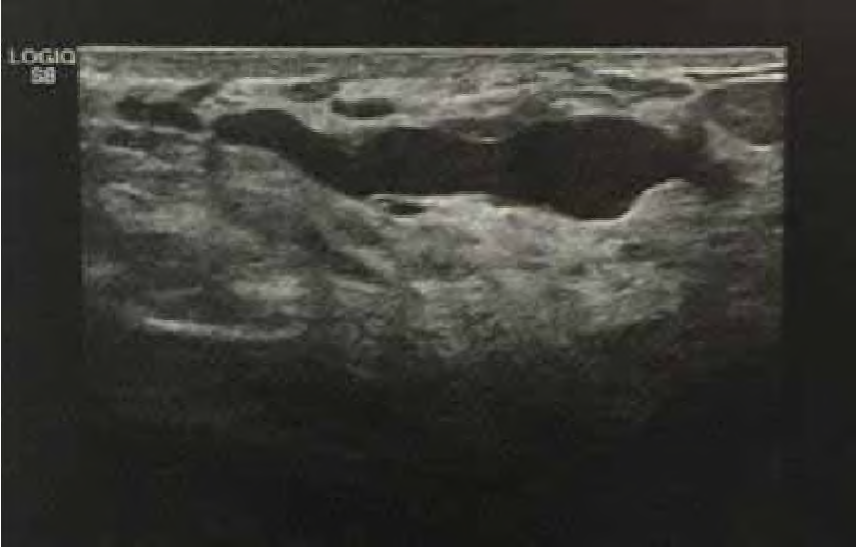

Mulher de 32 anos de idade queixa-se de fluxo papilar à esquerda, de coloração amarelada. Ao exame das mamas, observa-se fluxo papilar, espesso e amarelado, multiductal à expressão. A ultrassonografia é mostrada na imagem.

O diagnóstico é